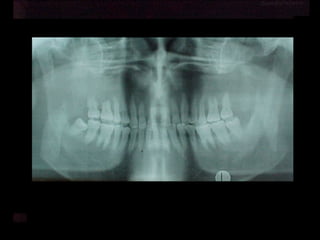

Se observa el número total de órganos dentarios incluyendo

terceros molares.

No hay tratamiento de conductos radiculares

Buen trabeculado óseo de tipo I